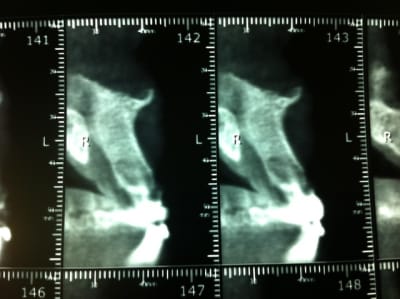

Patient venant en urgence avec bel abcès palatin entre 21 et 22.

Ras à la rétro sauf un petit dépassement sur 21. Gencive tuméfiée, violacée en vestibulaire de 21-22. La 21 a déjà eu un Rte il y a 4 ans.

Rien au sondage, mais en regardant de plus prés la rétro, je suspecte un trait de fracture en distal de 22...

Mis sous Antibio, plus de signe clinique. Prescription de cone Beam et surprise, belle image...

Voila, à priori le patient souhaiterait deux implants...

Que penses tu de la taille de la lésion?

Elle est quand même volumineuse. Tu penses qu'en greffe d'apposition pourrait être envisageable?